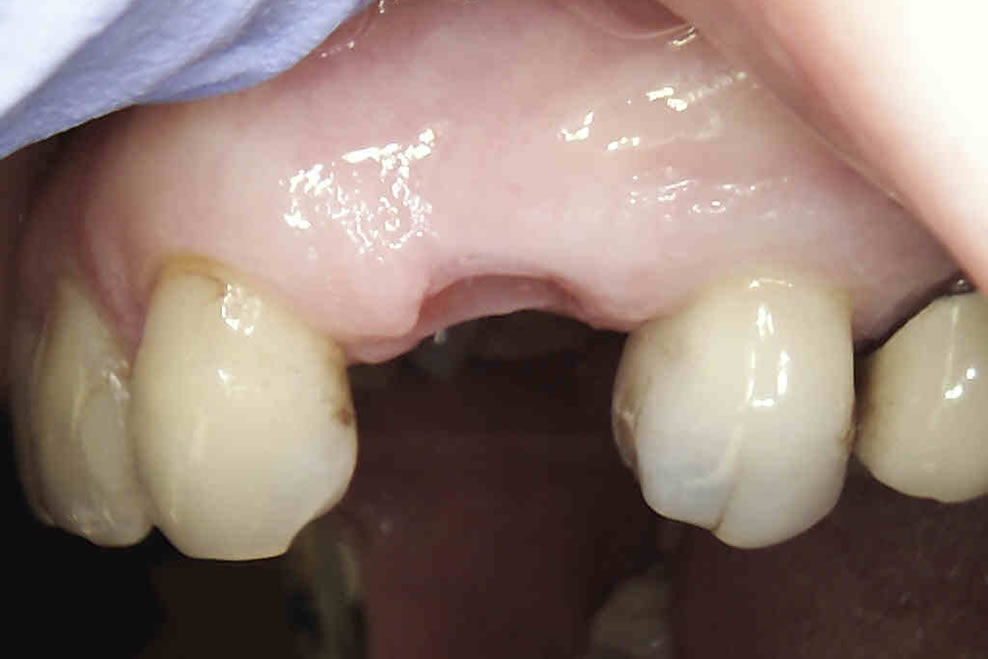

IMPLANTS FOR SINGLE & MULTIPLE MISSING TEETH

Dental implants are the best-known treatment to replace single or multiple missing teeth because they feel and behave just like natural teeth. After a while you won’t be able to tell the difference – even forgetting that they are there.

The procedure to place implants and replace a missing tooth or multiple teeth is straightforward as there is little need to treat surrounding teeth. Once a crown is placed over the implant it will appear indistinguishable from the natural teeth.